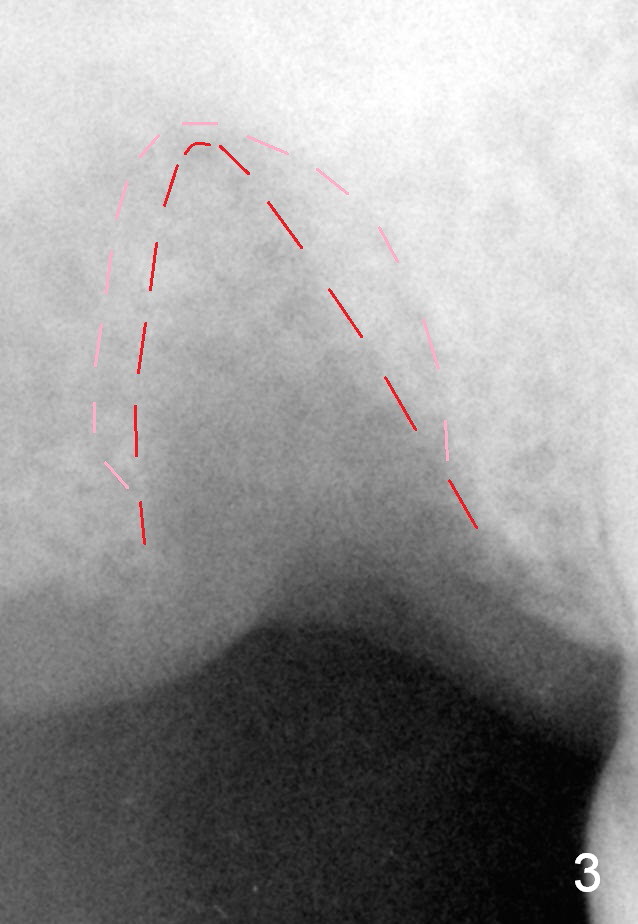

A 76-year-old man had the tooth #2 extracted (due to endo failure) 2 weeks ago (Fig.1). The socket looks "empty" (Fig.2 S, basis for osteotomes). It consists of the buccal (pink dashed line) and palatal (red) ones (Fig.3). In one word, the socket is pyramidal. It appears that a tapered implant is appropriate for the site. Clinically, the socket is healing with soft tissue covering the opening of the socket.